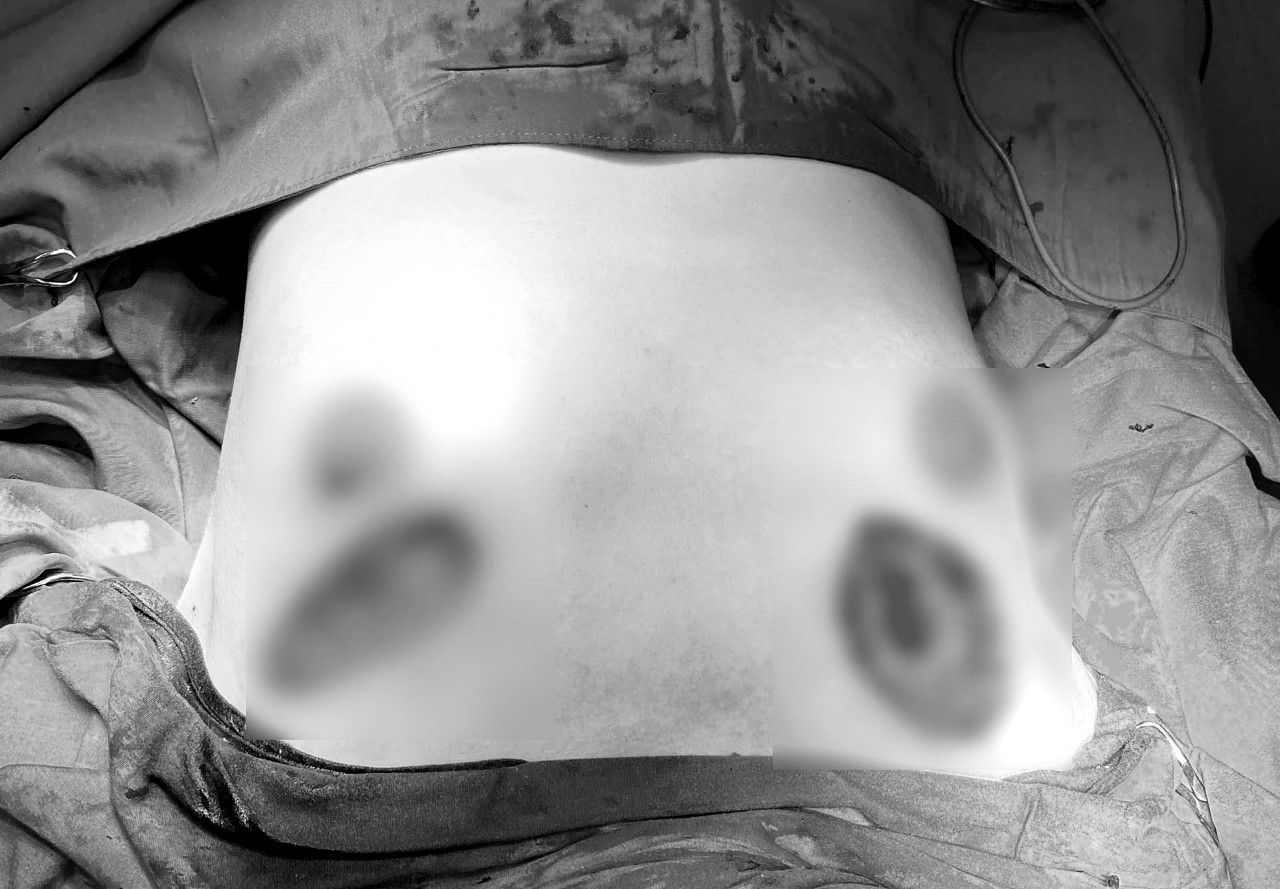

Nằm cùng phòng bệnh bị biến chứng do phẫu thuật thẩm mỹ không an toàn với bệnh nhân T. là bệnh nhân L.T.K.M (trú tại TP. Hồ Chí Minh) gặp biến chứng khi phẫu thuật làm quầng ngực.

Sau khi phẫu thuật tại cơ sở làm đẹp, vết thương của bệnh nhân không lành, rỉ dịch liên tục. Đi lại liên tục hơn 1 tháng ở cơ sở làm đẹp để “khắc phục” tình trạng này nhưng vẫn không cải thiện nên bệnh nhân quyết định đến Bệnh viện Chợ Rẫy để được xử trí.

Bệnh nhân được chẩn đoán hoại tử vùng phẫu thuật, ê-kíp điều trị Khoa Tạo hình thẩm mỹ đã xử trí triệt để và tái tạo lại vùng hoại tử

Hiện tình trạng sức khỏe của bệnh nhân M. đã ổn định và xuất viện ngày 22/9. Bệnh nhân T. đang tiếp tục được theo dõi, dự kiến xuất viện vào cuối tuần.